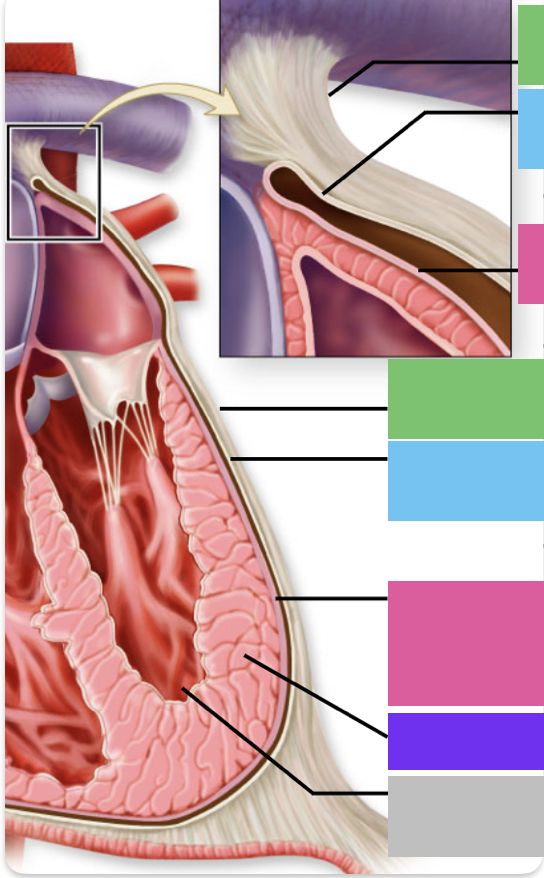

chordae tendineae

orange

papillary m.

blue

trabeculae carneae - only in ventricles

red

pectinate m. - only in R atrium

pink

fossa ovalis

grey

opening of coronary sinus